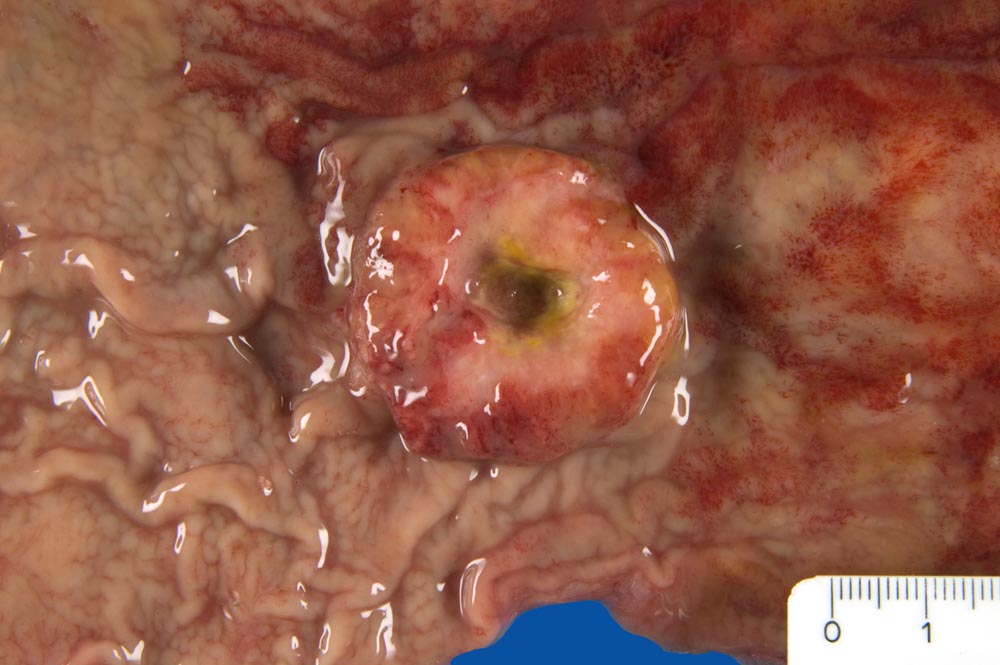

Makroskopisch können nach Borrmann (> 5050) polypoide Tumoren, ulzerierte Tumoren mit Randwall, ulzerierte Tumoren mit Invasion der Magenwand und diffus infiltrierende Tumoren (=Linitis plastica (> 3315)) unterschieden werden.

Die ersten beiden Typen entsprechen histologisch meist einem intestinalen Typ nach Lauren (> 1342). Diese Tumoren sind scharf begrenzt, bilden tubuläre oder papilläre Strukturen wie die Dickdarmkarzinome, sind meist assoziiert mit bekannten umweltbedingten Risikofaktoren und haben eine bessere Prognose.